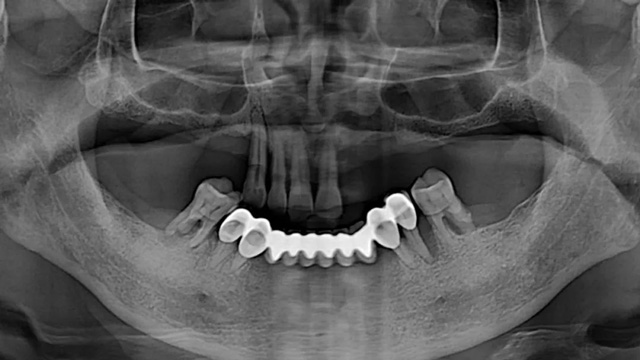

王先生全口種植后全景片(2024年4月/新橋口腔成都衣冠廟院區(qū))

由于王先生在上一家診所種下的6顆種植體比較短小,在力學(xué)方面達(dá)不到修復(fù)標(biāo)準(zhǔn),還有兩顆因?yàn)樗蓜?dòng)和頸部暴露無法使用,李陽軍醫(yī)生又加種了3顆更長更粗的,以確保長期穩(wěn)定性。由于骨量不足,有兩顆采用了傾斜植入以增加骨接觸的面積,目的也是為了更加穩(wěn)固,還有一顆因?yàn)樵恢霉橇刻睿臑樵谄渌恢梅N植,采取了高難度的術(shù)式。

王先生全口種植后戴冠